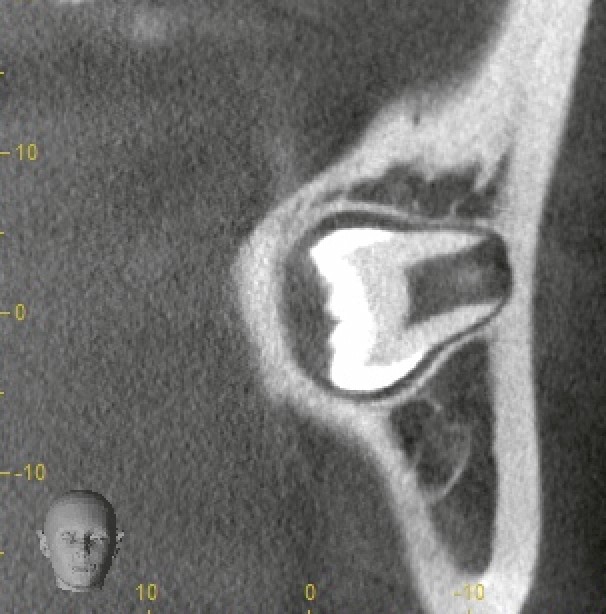

CT撮影で三次元的に評価

そこでCT撮影を実施。

結果は明確でした。

歯根が頬側、歯冠が舌側。

つまり、頬舌的に倒れ込んでいる埋伏智歯。

この情報があるかないかで、術式戦略は大きく変わります。

このタイプの抜歯で起こりやすい問題は:

・最終抜去時に歯冠が舌側骨に引っかかる

・無理な挺出で歯質破折

・舌側軟組織損傷リスク

今回も最終段階で歯冠が明らかにロックされることが予測できたため、

あらかじめ歯冠分割を行い、撤去方向をコントロール。

無理な力をかけず、安全に摘出しました。